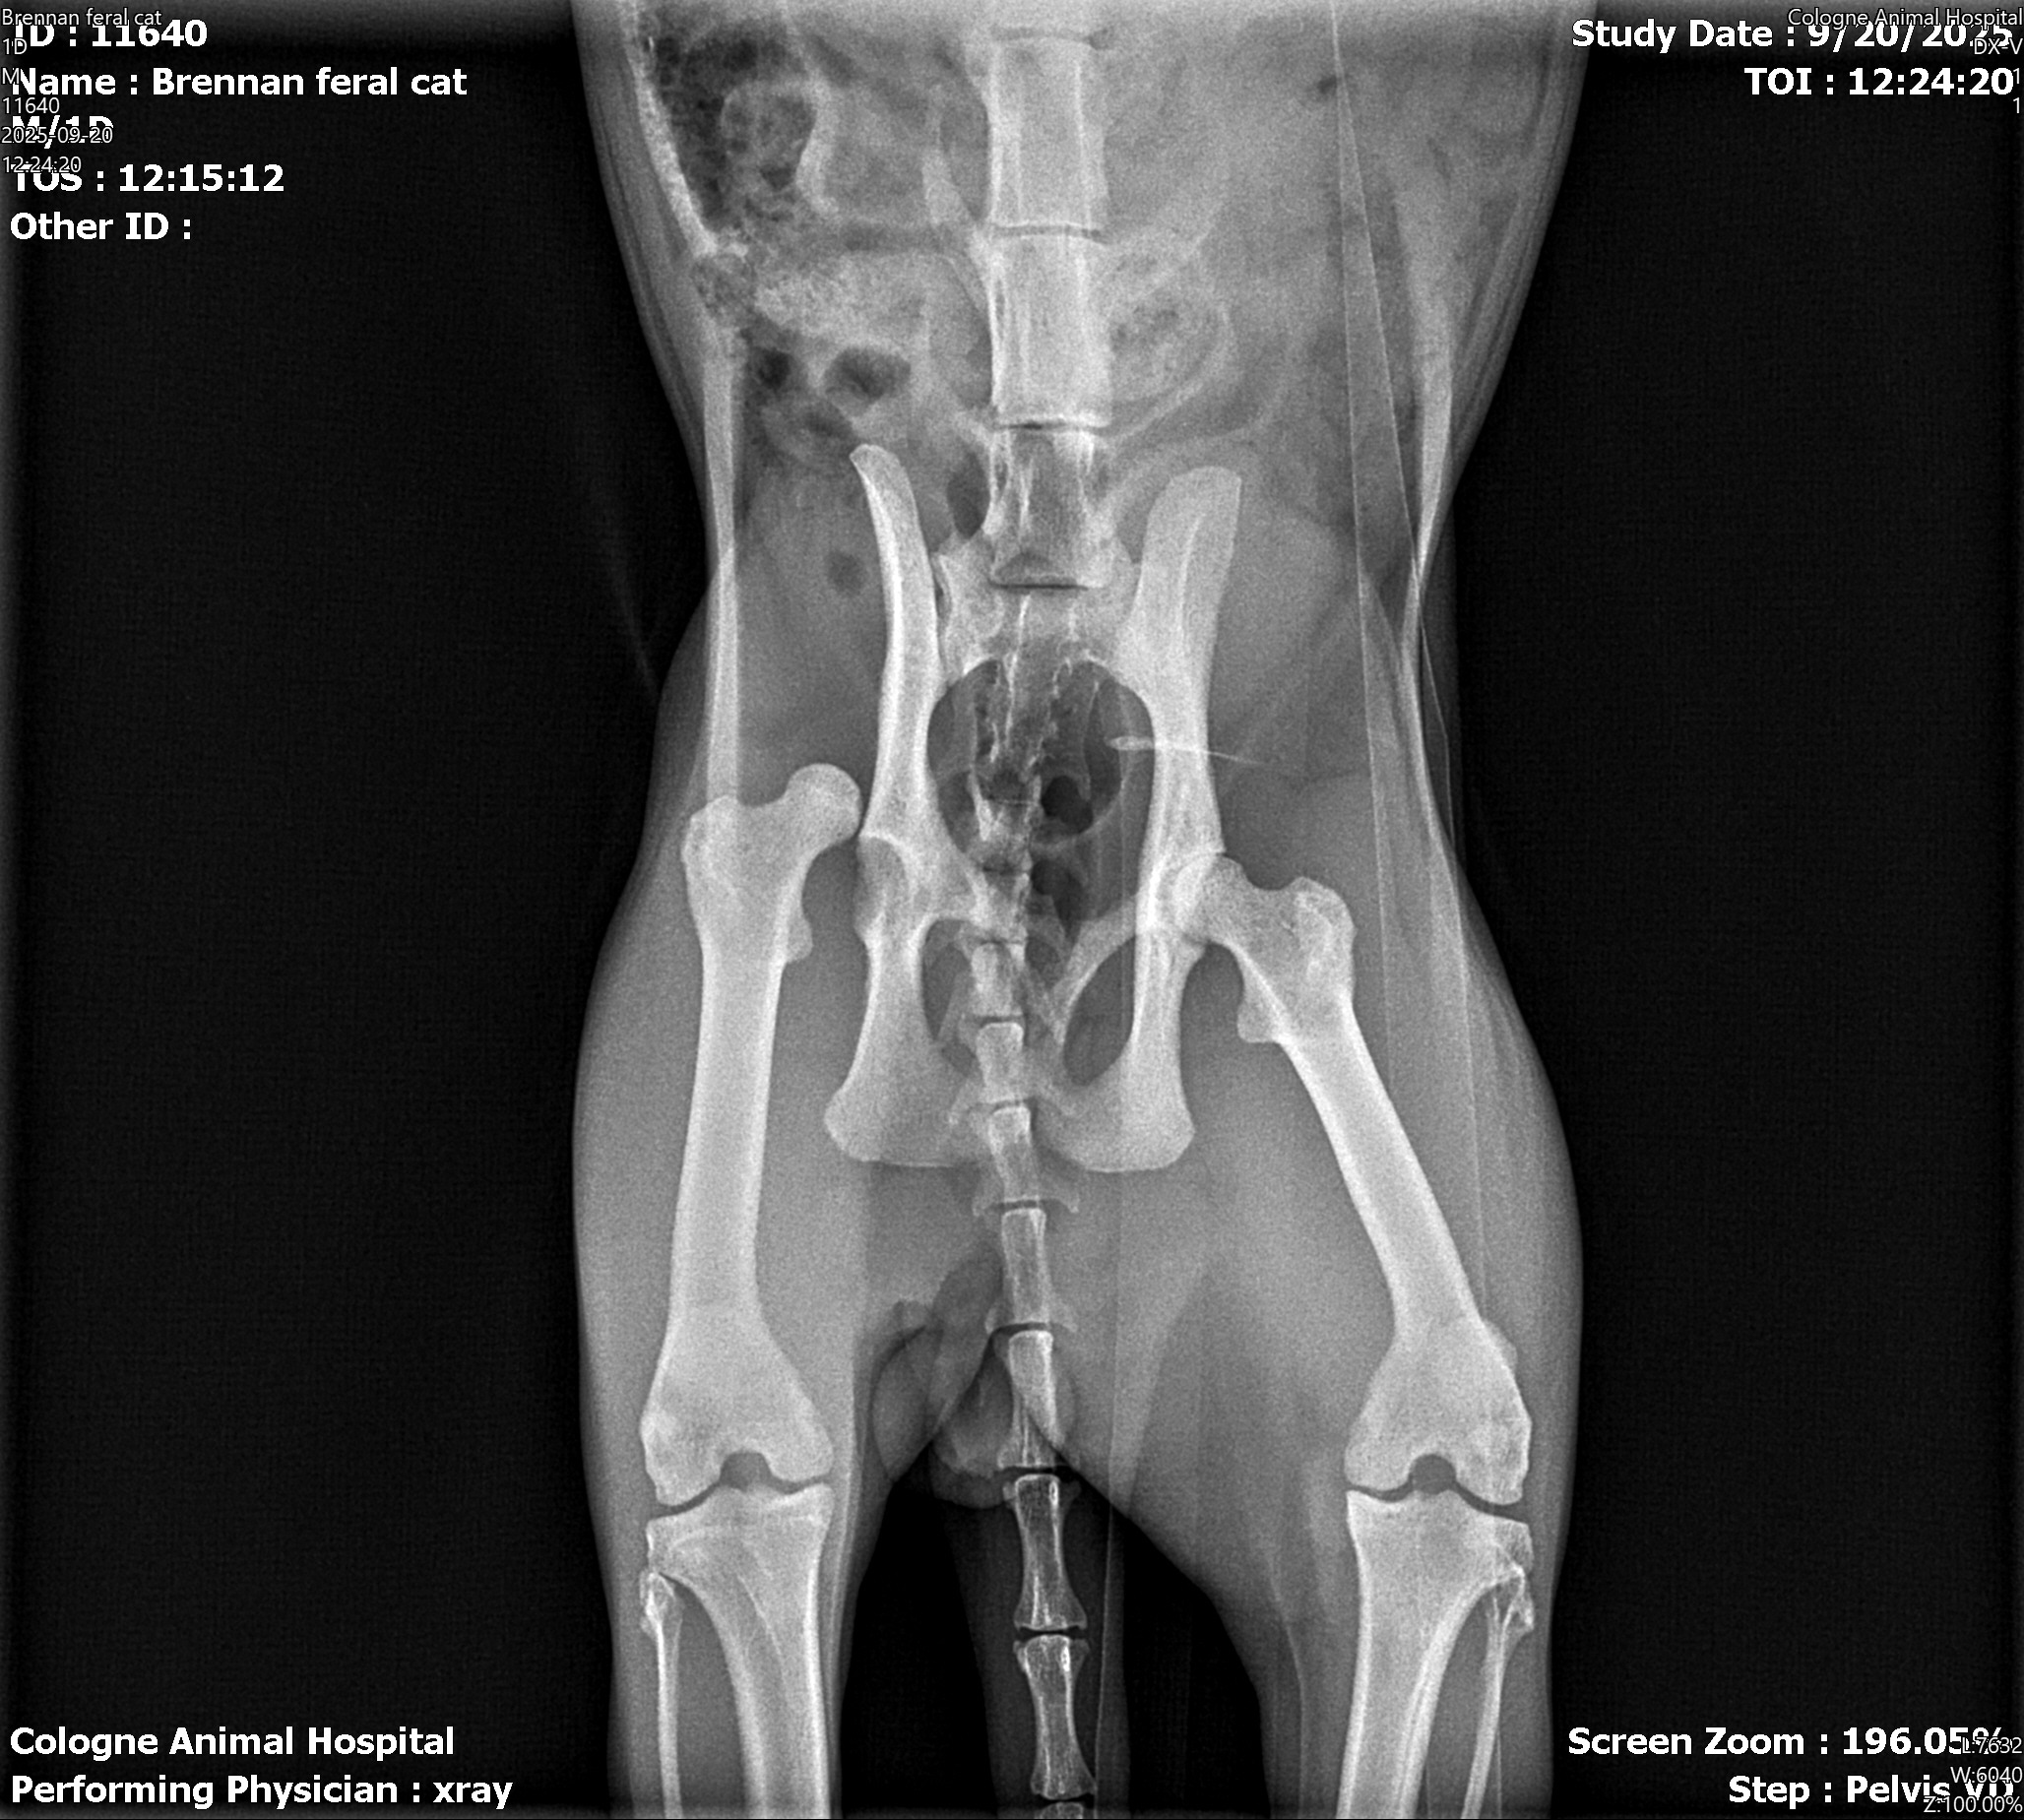

This is Sushi. I found him starving and injured next to the dumpster at my work plaza. I called every sanctuary and shelter in and around my county trying to find help for him. All were at capacity. My only other option was animal control. Being that he was injured, extremely malnourished, and in overall poor condition from the elements, he would more than likely be euthanized. He ran to me for help, and I don't believe the answer to abuse is to kill him. It has become my mission not to let that happen. He's an absolute sweetheart. He loves to cuddle, and more than anything, he loves a good bowl of sushi. I've taken him in for a check-up with my vet to see what was causing the limp in his back leg, and it seems that the ball of his right hip is not in the socket. I've attached the x-ray below. Because there's already been time between his injury and me finding him, the vet is unable to reset the joint. He will need a surgery with a starting cost of $4,500. Unfortunately, I don't have a credit limit high enough to make this happen. He is currently on medication to help with the pain, but this is far from a long-term solution, and he will need surgery soon. I'm not one to ask for help, but I will do whatever it takes to save his life. Anything is appreciated more than you know.